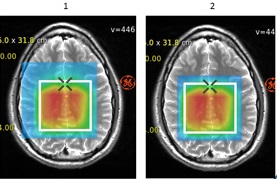

Figure 3. Metabolite map display

Table 1. Image legend Number Description 1 Show all voxels inside Pressbox is not selected and therefore metabolite maps display on the whole image. 2 Show all voxels inside Pressbox is selected and therefore metabolite maps only appear on the entire image. - The Show all voxel inside Pressbox toggles the spectra that appear in voxels. Note that you must draw first an ROI around the desired voxels.